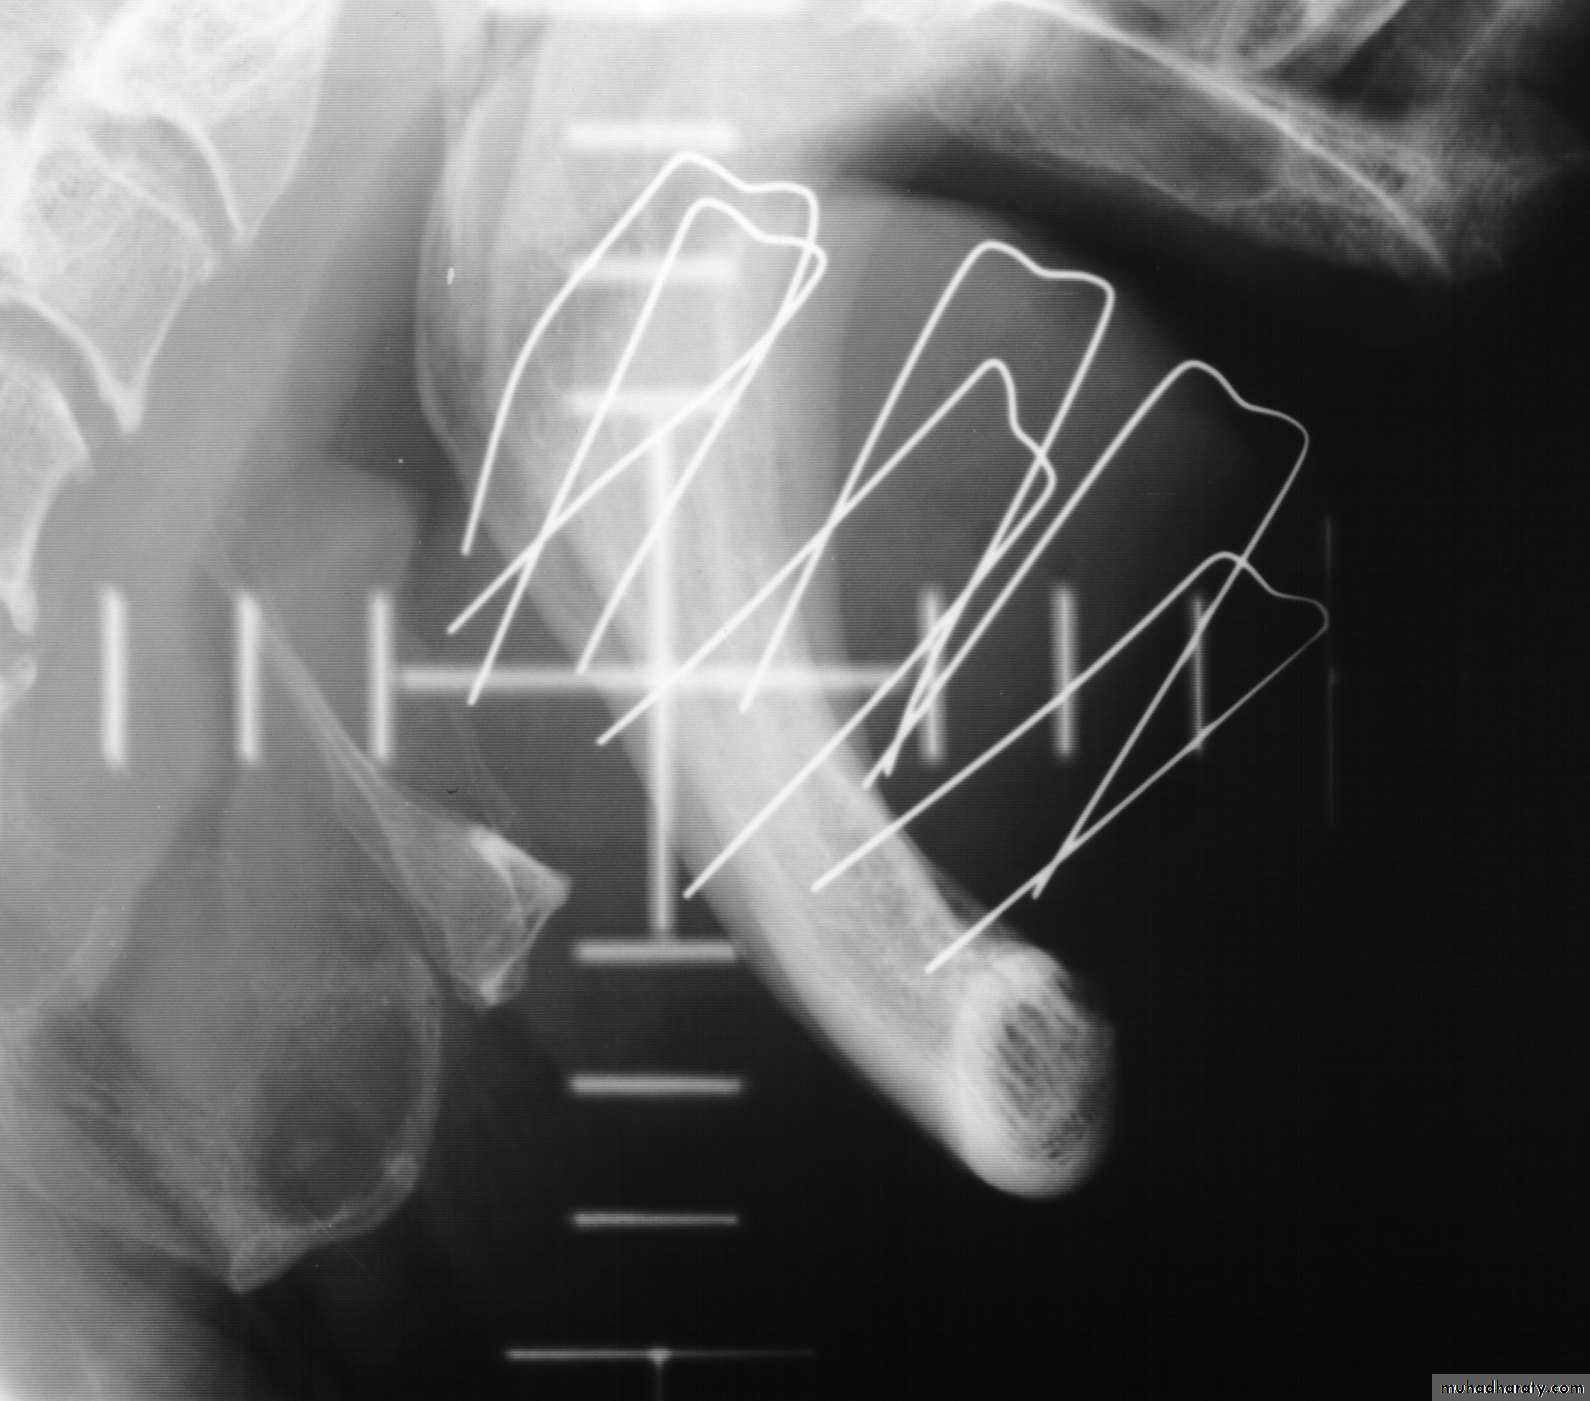

Interstitial treatments

192Ir (Iridium)Breast, anal and vaginal implants using iridium wire in steel needles

Tongue implants using hairpins